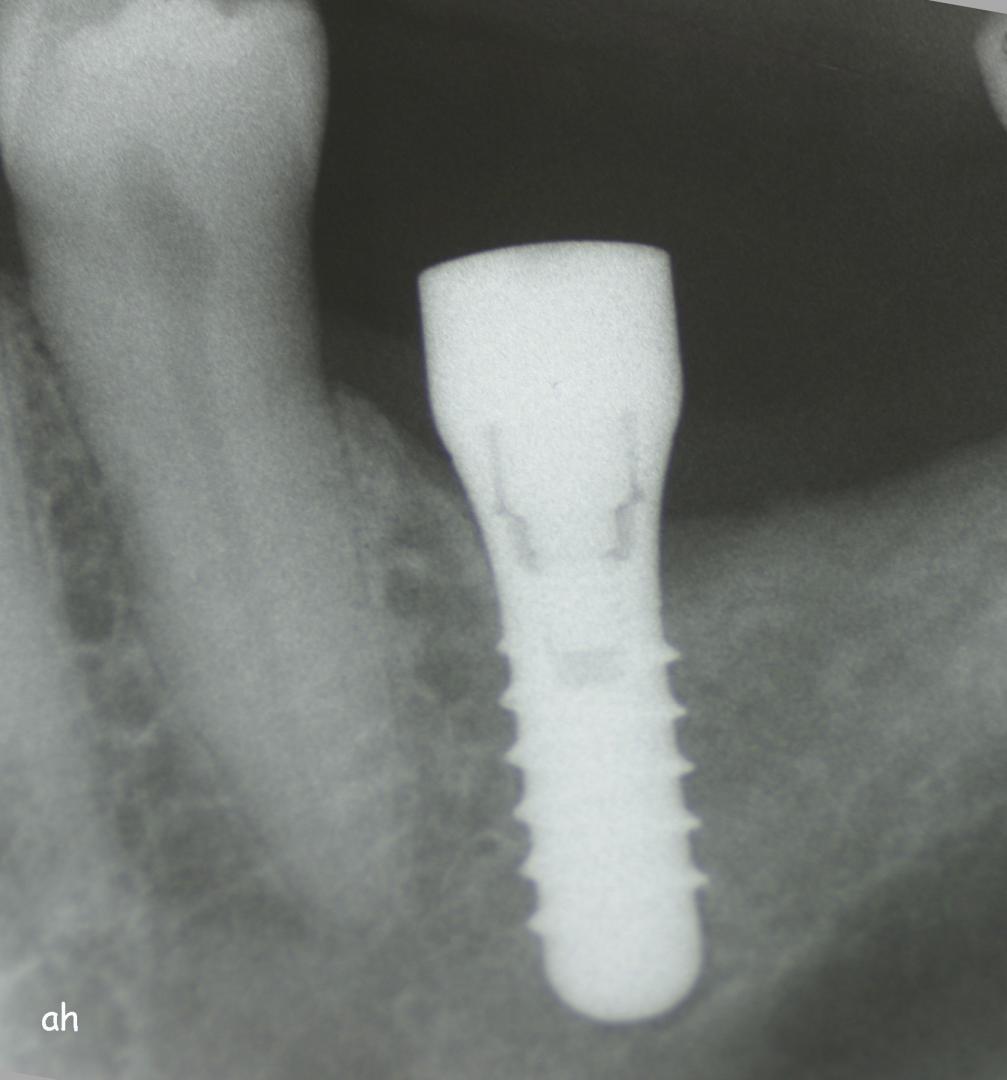

Exemple 14: Il est prévu de mettre un implant entre la molaire et prémolaire, mais le sinus se trouve à moins de 4 mm de la surface. Il faut donc relever le sinus avec une greffe d'os

Exemple 14: Un petit puits d'accès est créé afin d'atteindre le sinus, notez la membrane sinusienne.

Exemple 14: La fine membrane sinusienne est relevée, puis de l'os mélangé à de l'os artificiel est introduit dans la cavité.

Exemple 14: La cavité est maintenant remplie.

Exemple 14: Radiographie post chirurgicale.

Exemple 14: 6 mois plus tard, l'implant est introduit dans cette greffe sans toucher le sinus.